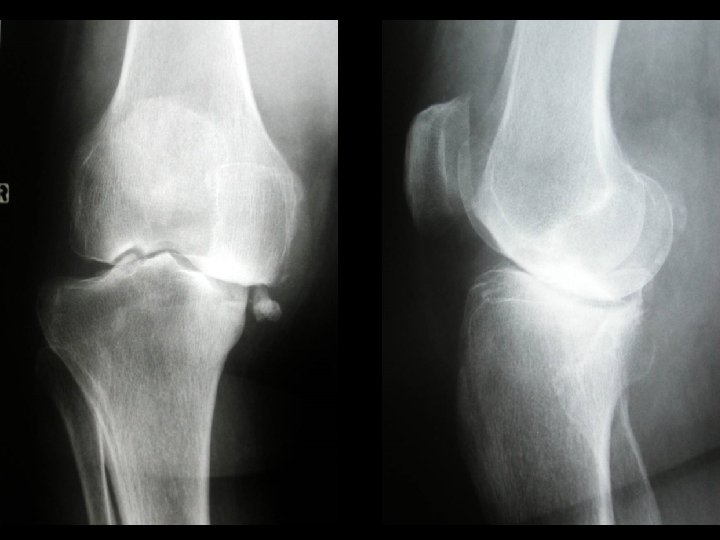

Our experience 527 total knee replacements with mobile bearing Period 1987 - 2005 48% left knee, 52% right knee 94 male, 433 female

Revisions One LCS and one Genesis II because of aseptic loosening of femoral component Two revisions because of traumasupracondylar femoral fracture in one and tibial fracture in the second One Polyethylene dislocation